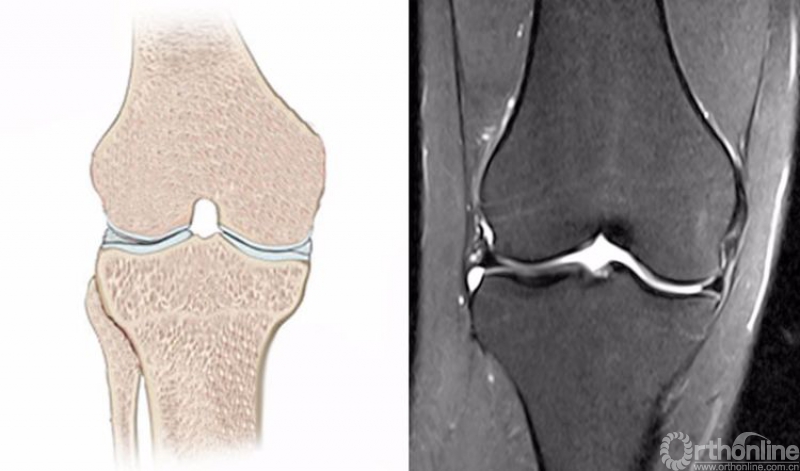

正常的膝关节进行MRI扫描时,不管任何一个序列,其骨髓信号一般T1WI呈均匀一致的灰色,T2WI及STIR呈均匀一致的黑色。

1.膝关节冠状位的正常MRI图像